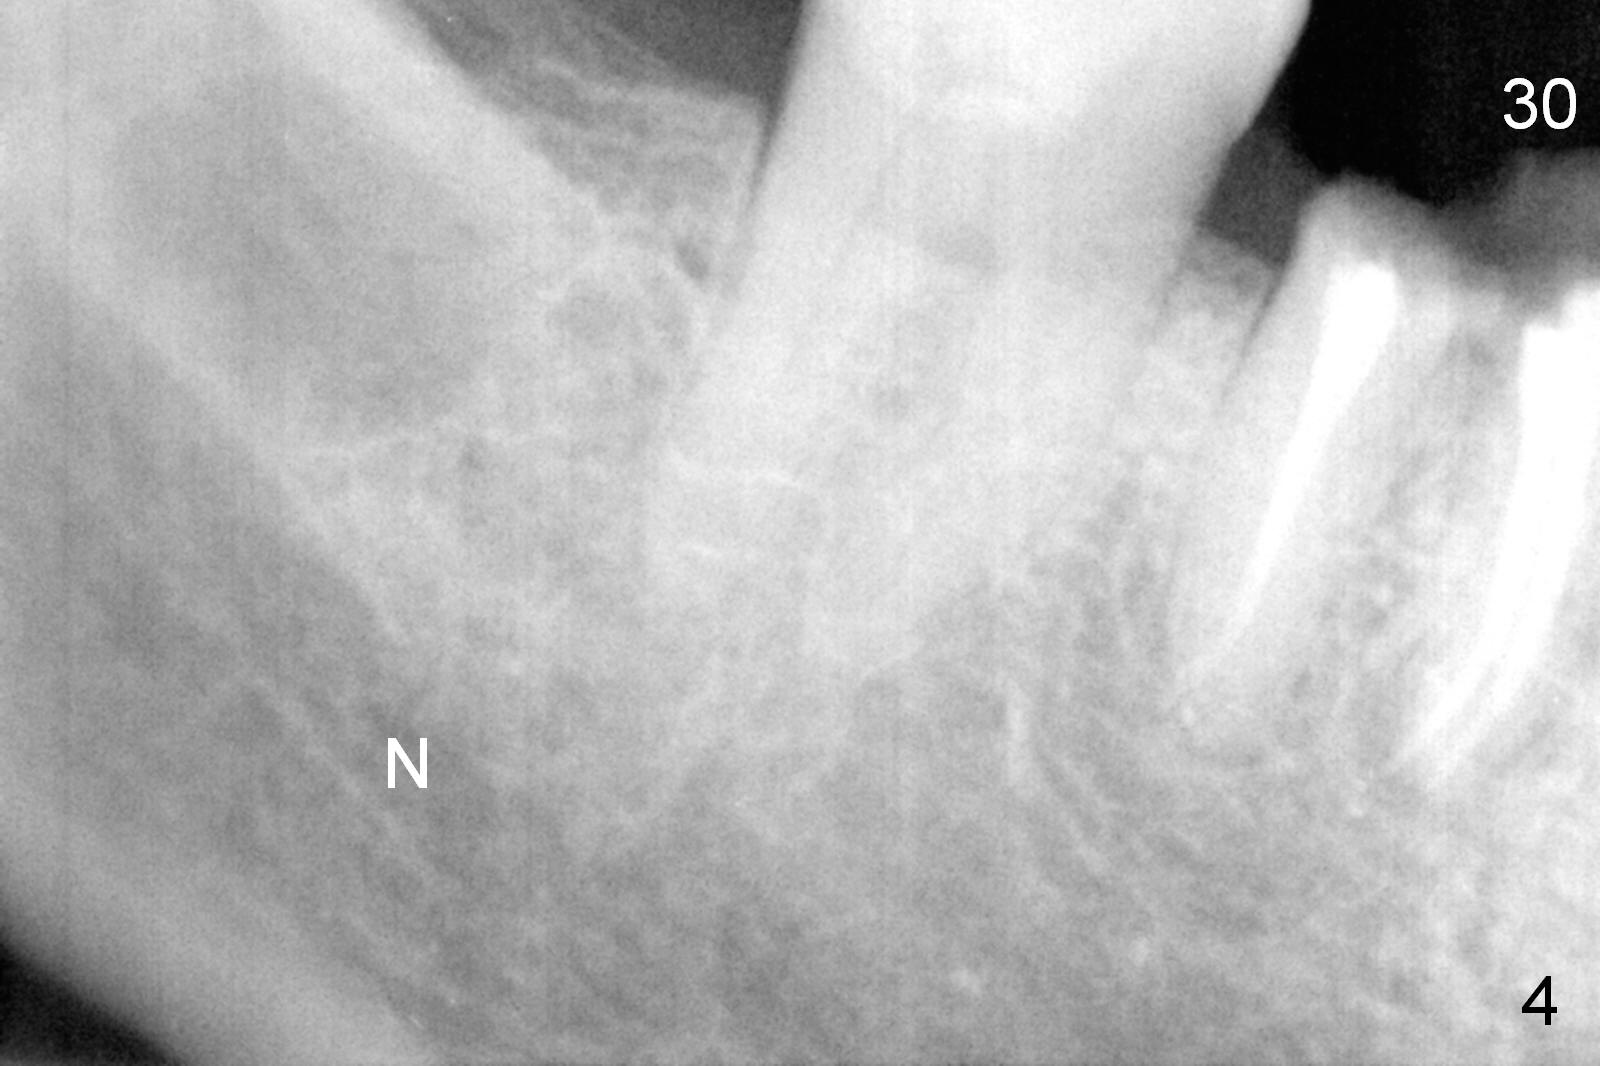

A 68-year-old lady (WQ) had CT taken 3 years ago (Fig.1-3), which show 3 roots (M: mesial; DB: distobuccal; DL: distolingual) of the lower right 1st molar and large caries (C). Recently the tooth fractures after root canal therapy (Fig.4-6).